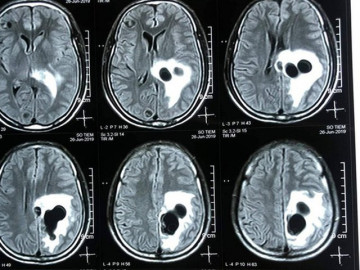

Do ăn tiết canh, một người đàn ông ở huyện Quỳ Hợp, Nghệ An đã bị liệt nửa người vì não có nhiều sán làm tổ gây phù não.